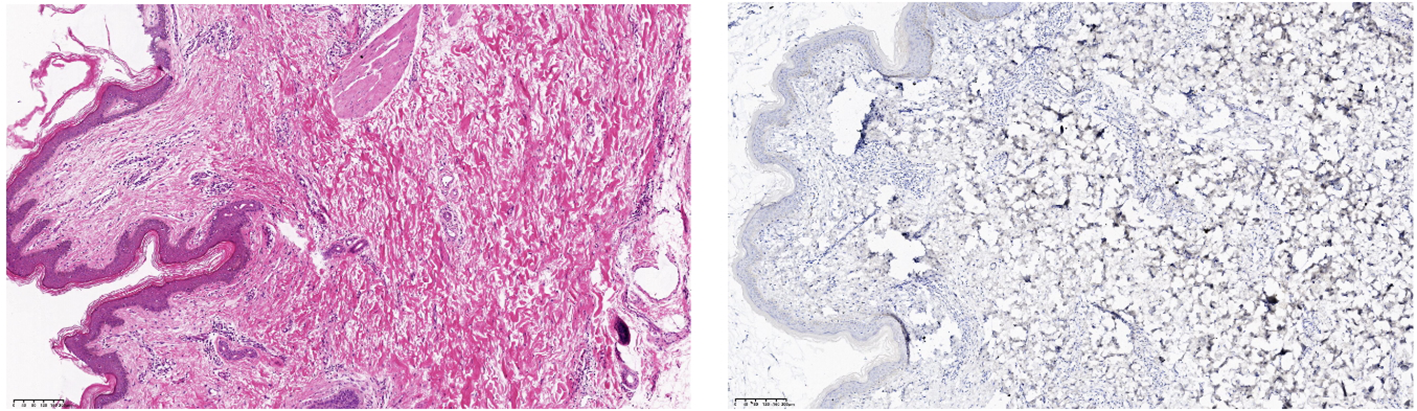

After obtaining informed consent from the patient, tirilizumab 200 mg/dose was added to the original regimen on September 19, 2023. The medication was administered once every three weeks. After nine consecutive uses, the patchy rash at the root of the left thigh reduced in range, the hard nodules disappeared, and the color became significantly lighter (Figure 2). Additionally, there was no swelling in both calves, indicating a promising therapeutic effect. Despite the absence of symptoms indicative of thyroid dysfunction, namely weakness, fatigue, facial swelling, or muscle pain, thyroid function tests revealed an elevated thyrotropin (TSH) level of 16.19 μIU/mL, a triiodothyronine (T3) level of 1.51 nmol/L, and a total thyroxine (T4) level of 107.09 nmol/L. The endocrinologists diagnosed PD-1-induced hypothyroidism and prescribed 25 μg levothyroxine tablets for treatment. To assess the therapeutic effect, skin biopsies were performed on the macules on the root of the thighs and on the calf of the left lower limb, respectively. Pathological assessment revealed chronic vasculitis (Figure 3). and the patient achieved complete remission. The timeline of patient diagnosis and treatment is shown in Figure 4.

Figure 3. (Skin of left calf and thigh) Chronic vasculitis. Immunohistochemistry: CD34 (vascular +), D2-40 (vascular +), ERG (vascular endothelial +), HHV-8 (-), Ki-67 (few +).